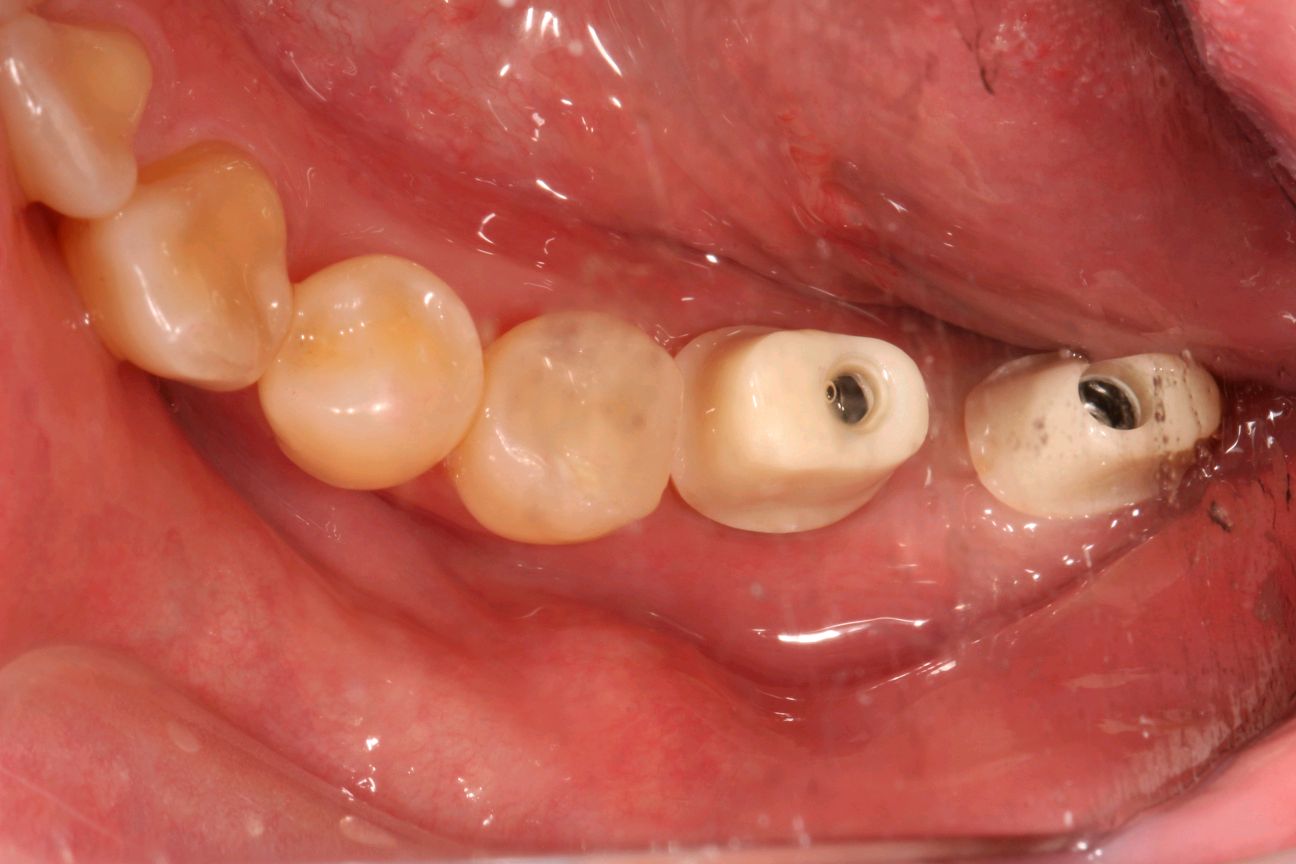

术中